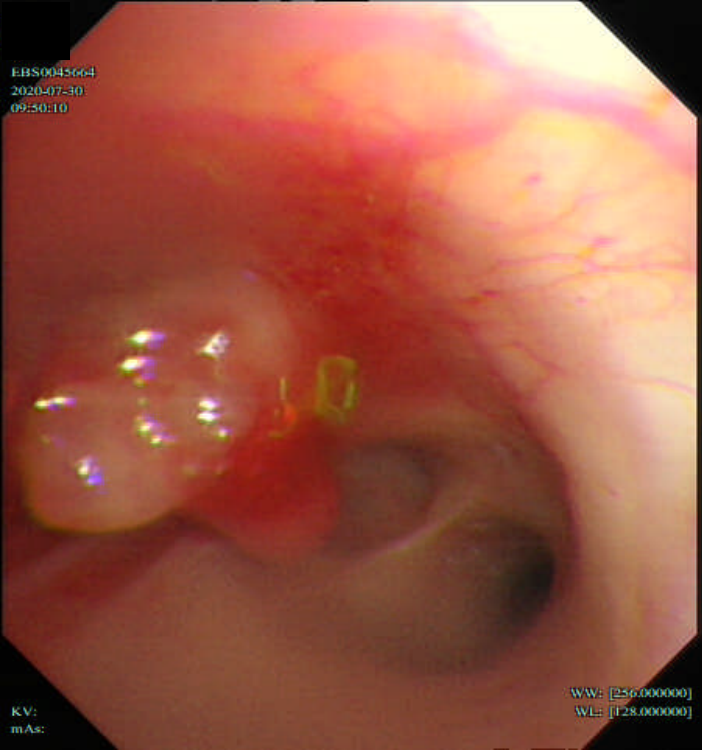

纤维支气管镜活检(2020-07-30):(左上上支开口活检)鳞状细胞癌。免疫组化:CK7(-), P40(+), TTF-1(-), CK5/6(+), Napsin A(-)。

图8:2020-07-30,基线期纤维支气管镜